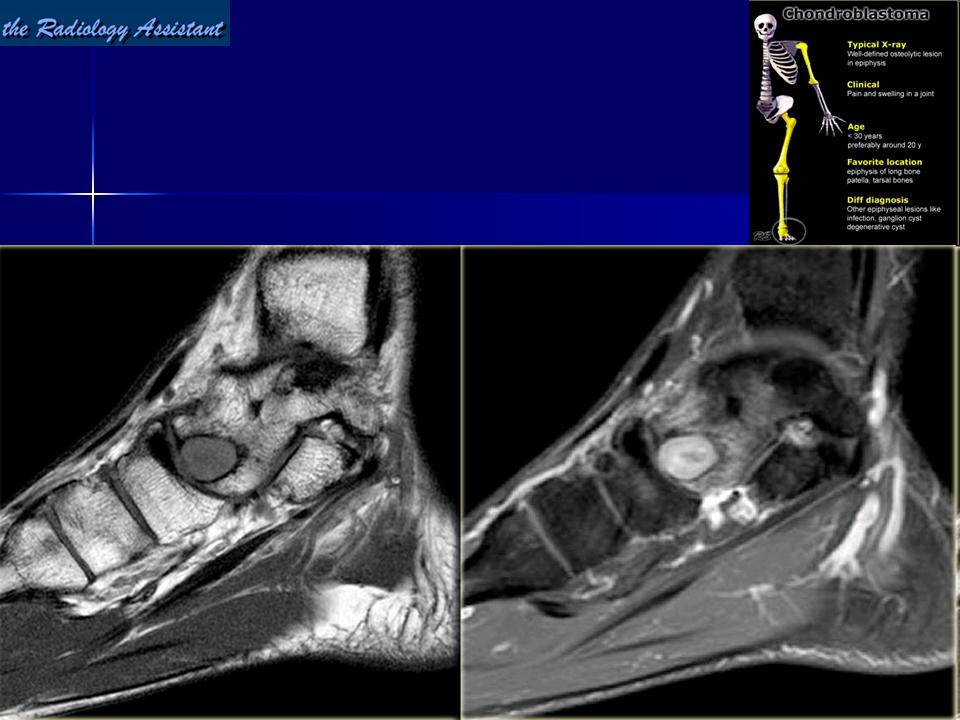

Хондробластома — это редкая доброкачественная опухоль, локализующаяся, главным образом, в эпифизе и отличающаяся своеобразным клеточным составом. Ткань новообразования представлена овальными, округлыми и веретеновидными клетками, напоминающими незрелые хондроциты (хондробласты). Зрелый гиалиновый хрящ определяется лишь в некоторых опухолях. Возраст больных варьирует. Мужчины поражаются в два раза чаше женщин. Пациенты предъявляют жалобы на боли в течение нескольких месяцев или лет, у некоторых больных определяются внутрисуставной выпот, припухлость и ограничение движений. Наиболее типичная локализация опухоли — проксимальные эпифизы плечевой и большеберцовой костей, а также дистальный эпифиз бедренной кости. У 20 % больных опухоль развивается в плоских или коротких трубчатых костях, преимущественно в пяточной и таранной. Изредка поражаются кости лицевого черепа, в том числе височная. В большинстве случаев новообразование выходит за пределы эпифиза и распространяется на метафиз. На фоне остеолиза обнаруживаются рассеянные участки обызвествления в виде пунктирных линий, а также разреженный трабекулярный рисунок. Хондробластома, как правило, не выходит за пределы кости, но изредка проникает в полость сустава. В процессе роста опухоли иногда возникает вторичная аневризматическая костная киста.

Хондробластома (кальцифицирующаяся гигантоклеточная опухоль, эпифизарная хондроматозная гигантоклеточная опухоль) - доброкачественная, хрящевая опухоль, развивающаяся в эпифизарных отделах костей. В настоящем исследовании хондробластома выявлена у 5 мужчин и 3 женщин.

Рентгенологическая картина. Хондробластома выглядит как небольшой, от 3 до 6 см литический очаг, центрально или эксцентрично расположенный, с четкими контурами, занимающий около половины площади эпифизарной зоны. Хондробластома плоских костей и мелких трубчатых костей больших размеров, может сопровождаться припухлостью мягких тканей, вздутием кости и периостальной реакцией. Распространение процесса на метафизарную зону встречается часто.